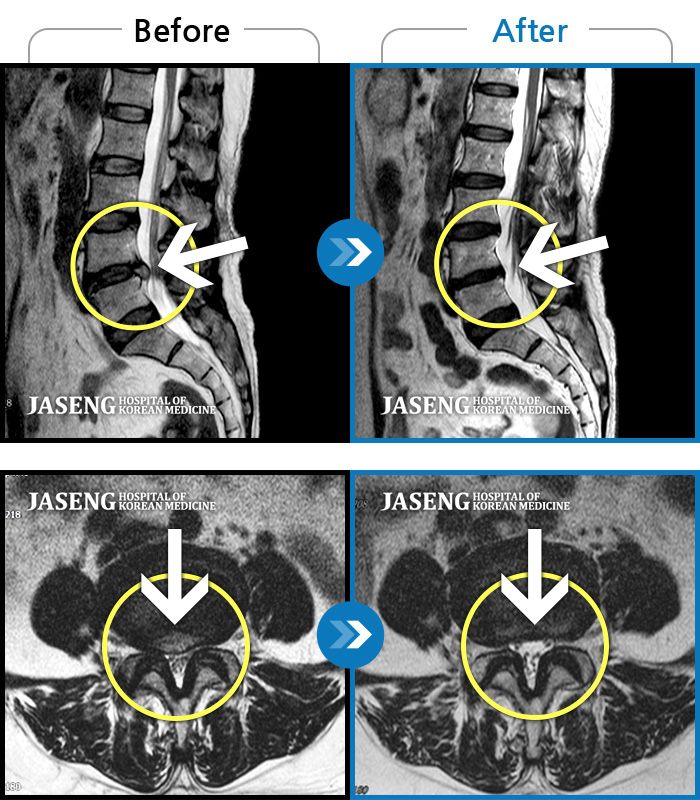

내원 당시 추간판 탈출 및 척추관 협착증으로 잠자기 어려울 정도의 요통 및 오른쪽 골반~종아리 저림으로 일상생활이 어려우셨던 분입니다.